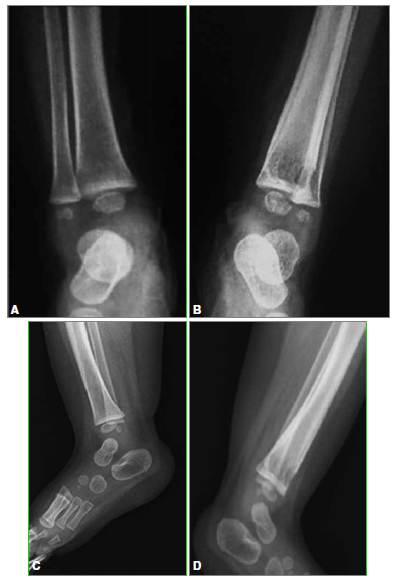

Lipoblastoma: una causa inusual de tumoración del pie en niños

65-73

Acceso mediante suscripción PDF Acceso mediante suscripción PDF_EN (English) Acceso mediante suscripción Figura 1 Acceso mediante suscripción Figura 2 Acceso mediante suscripción Figura 3 Acceso mediante suscripción Figura 4 Acceso mediante suscripción Figura 5 Acceso mediante suscripción Tabla 1 Acceso mediante suscripción HTML